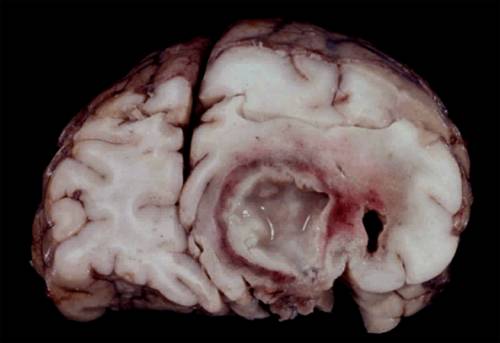

比如说,当一些细菌或真菌感染了脑实质、形成脑脓肿时,被感染的脑组织会出现坏死,接下来坏死的组织逐渐增多、融合,最终可能就会形成一个“大空洞”,里面漂浮着感染菌、坏死组织的碎片,以及炎症细胞。

脑脓肿实际长啥样?

图片来源:imagestack.co